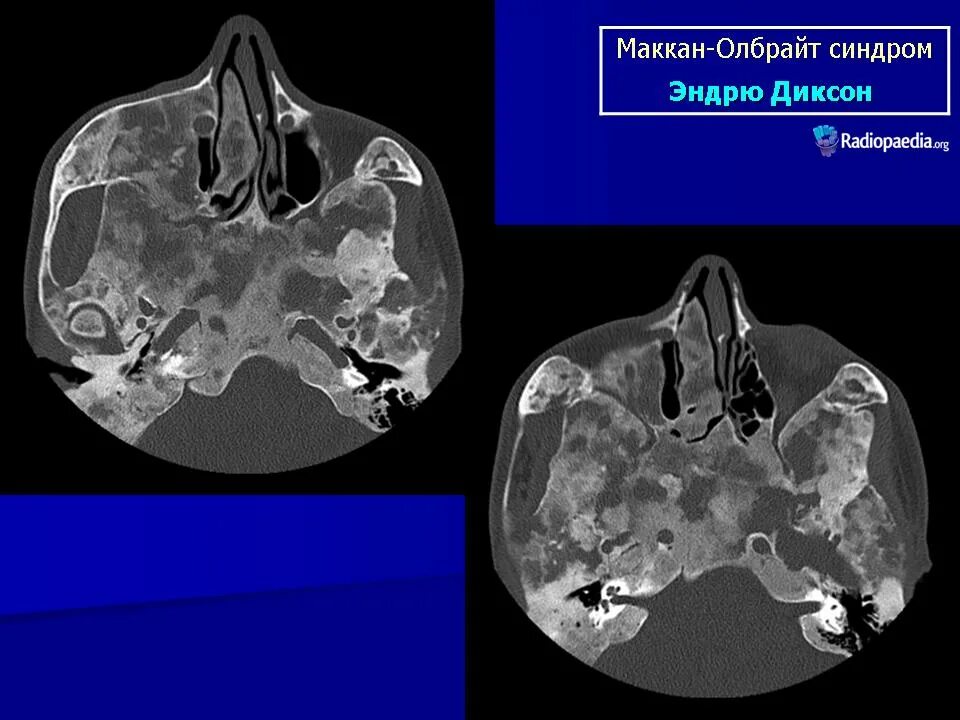

Синдром олбрайта